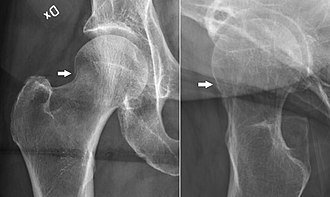

Dr. Ankur Rana is an expert at fracture management. With his best experience and knowledge in trauma management, treatment of all types of fractures is done at Summit Orthopaedic Hospital. State of art infrastructure and imaging technology enable us to do minimally invasive surgeries to improve patient outcome and speed patient’s recovery post operatively.

Complex fractures, intraarticular fractures, pelvi-acetabular fractures, multiple fractures and polytrauma patients have excellent outcome post surgery at our institution. We also provide excellent management of Periprosthetic fractures.